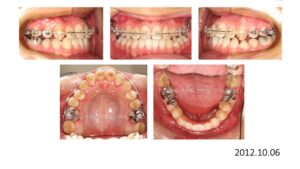

8歳からリンガルアーチで拡大を開始し、3年間拡大を続け、12歳でマルチブラケットを付けて治療を開始したそうですが、開咬が治らないためにアンカースクリューを4本打って治療を続けたとのことです。

こんなスクリューじゃあ何の意味もありません。

まさにやっている事がデタラメです。

ひろ矯正歯科に来られた時には、口腔内清掃状態は悪く、全ての歯が齲蝕でボロボロ、要治療でした。

検査、診断の結果、この患者さんは矯正のみで治療することは不可能、上下顎骨の離断が必要で外科矯正となりました。